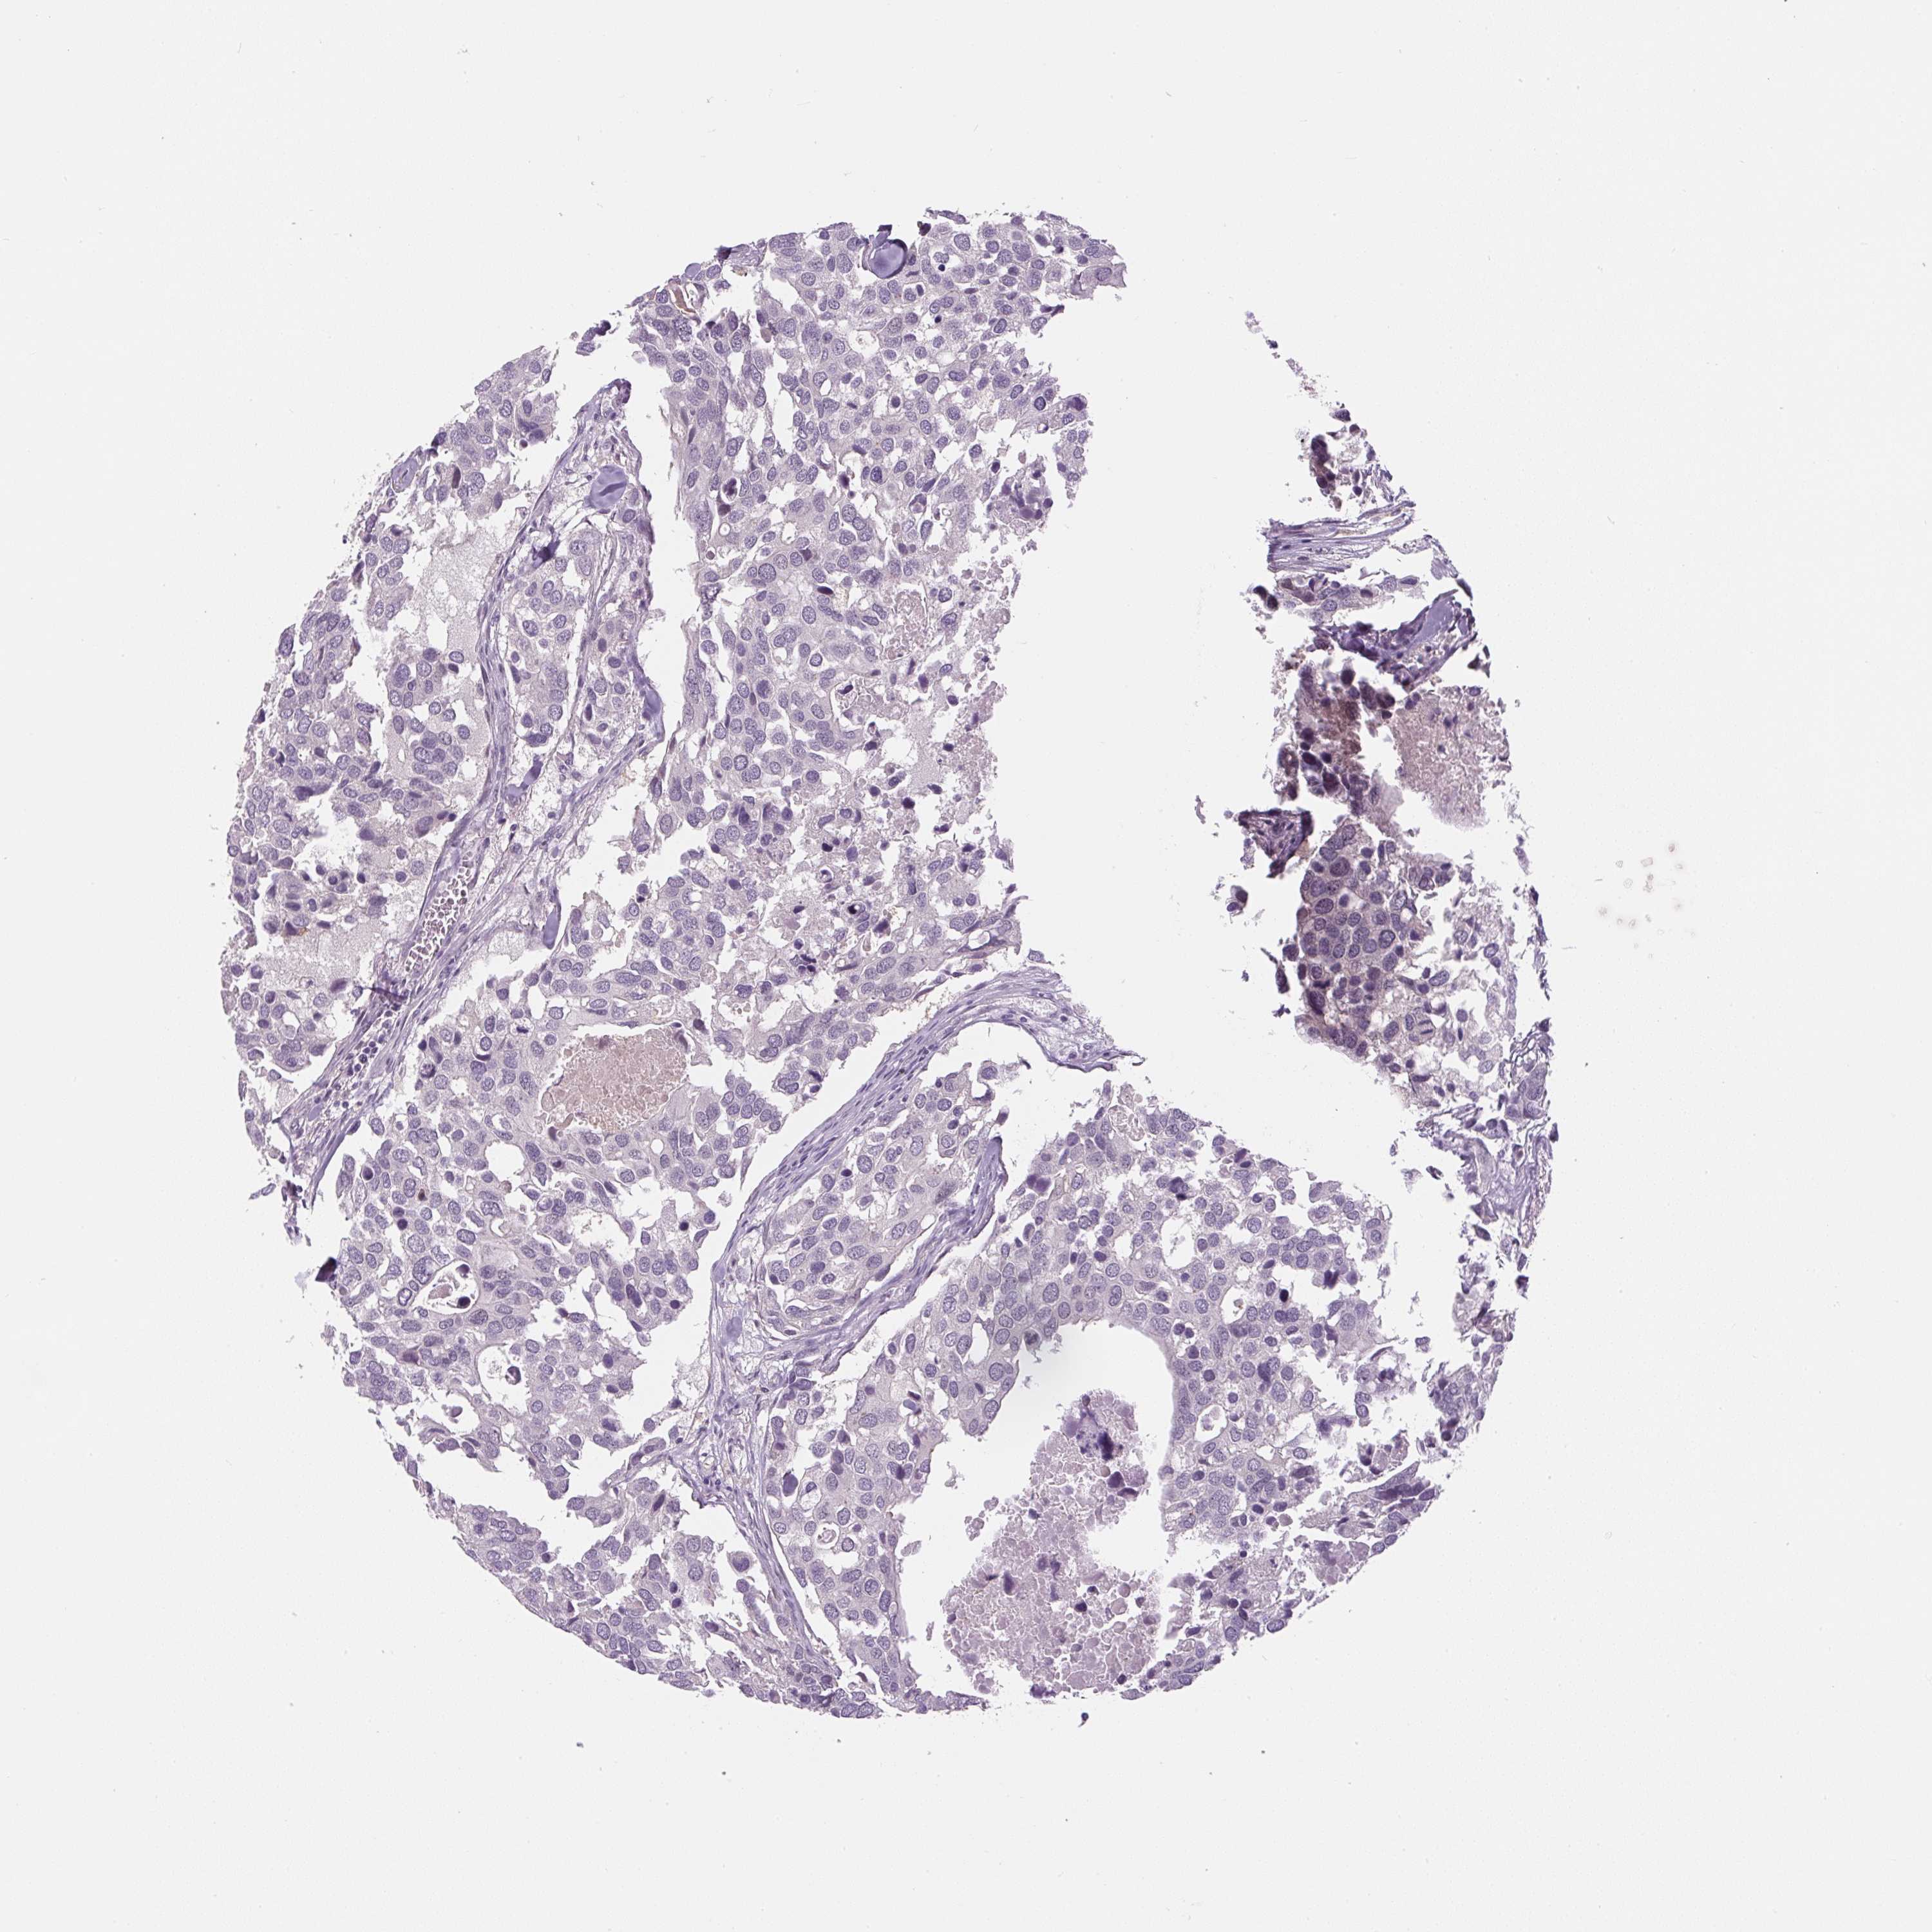

CANCER BREAST CANCER Show tissue menu

BRCA TCGA BRCA VALIDATION PROTEIN EXPRESSION